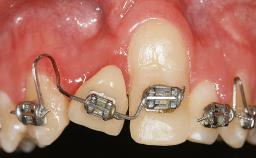

GBR and Soft-Tissue Augmentation Following Explantation to Rehabilitate a Soft- and Hard-Tissue Defect

It is sometimes necessary to remove and replace compromised implants. This case is a clear example of the need for multiple steps to achieve an optimal therapeutic result for patients with non-salvageable implants. It illustrates how the lost soft and hard tissues were rebuilt in a sequence that improved the healing of the hard tissues and assured their long-term stability. The 35-year-old healthy patient presented with clinical attachment loss on the proximal and lingual surfaces of the natural dentition. Some gingival recession was present on natural teeth, particularly in the posterior sextants (S1, S3, S4, and S6).

Soft Tissue Grafting Staged